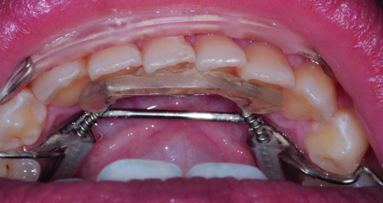

The Inman Aligner works by employing dual forces―pushing and pulling simultaneously. The single, removable device utilises a lingual coil spring that exerts pressure on the teeth that need repositioning and a labial bar that reverses the same pressure. These components work together to squeeze teeth into place. Compared with traditional orthodontic braces, the Inman Aligner offers a more discreet, faster and less expensive way to achieve excellent results in the ‘social six’ region of the mouth, with average treatment times of between six and 18 weeks. The forces employed by the Aligner mean that it works a lot faster than the retainer-style treatment employed by other clear alignment systems, compensating for the fact that it is ever so slightly less discreet. However, the fact that the device is removable often makes up for this in the mind of the patient.

Of course, not every case is suitable for treatment in this way, and case selection is critical. The Inman Aligner is only suitable for correcting anterior teeth. Large side shifts, intrusions and extrusions cannot be treated in this way. However, rotations, tipping, buccolabial movements and diastema closures in protrusive cases are all possible, as long as case selection criteria have been met.